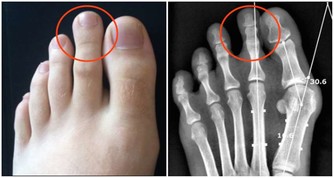

為什麼糖友那麼害怕“糖尿病足”呢?

因為如果糖尿病足病情較重,患者只能進行截肢手術。

小小感染,也易引發糖尿病足

在我國,大約85%的下肢截肢是糖尿病足引起的。